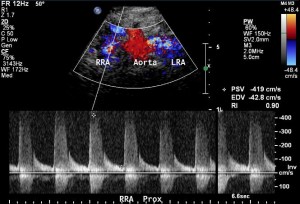

The midline approach is ideal for obtaining blood flow velocity in the proximal aorta. This velocity is later used to calculate the renal to aorta flow ratio. An increased ratio suggests significant renal artery stenosis. The velocity in the proximal aorta should be measured at the level of the origin of the superior mesenteric artery. The superior mesenteric artery is often easier to identify when the aorta is elongated as its course is often parallel to that of the aorta. Sampling of the superior mesenteric artery waveform should show a high resistant waveform, if the patient has indeed fasted.

Tip: the superior mesenteric artery waveform is usually higher velocity than the aorta. Choose to locate the pulse-wave cursor slightly proximal or distal to the superior mesenteric artery origin to avoid overlap between waveforms.

The next step is to identify the renal arteries. Each renal artery should be sampled in its origin and proximal, mid and distal portions. The distal portion of the renal artery is often difficult to obtain from the midline even in easy renal artery ultrasound. The proximal portion is difficult to obtain from the flank and therefore effort should be made to obtain it from the midline.

Sometimes the images are less than optimal. If there is uncertainty, images should not be acquired. However, if the renal artery can be identified coming in from the rest of the noise, then it can be sampled: